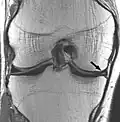

| Proton density weighted | PD | Long TR (to reduce T1) and short TE (to minimize T2).[7] | Joint disease and injury.[8]

Proton density

Proton density (PD)- weighted images are created by having a long repetition time (TR) and a short echo time (TE).[36] On images of the brain, this sequence has a more pronounced distinction between grey matter (bright) and white matter (darker grey), but with little contrast between brain and CSF.[36] It is very useful for the detection of arthropathy and injury.[37]